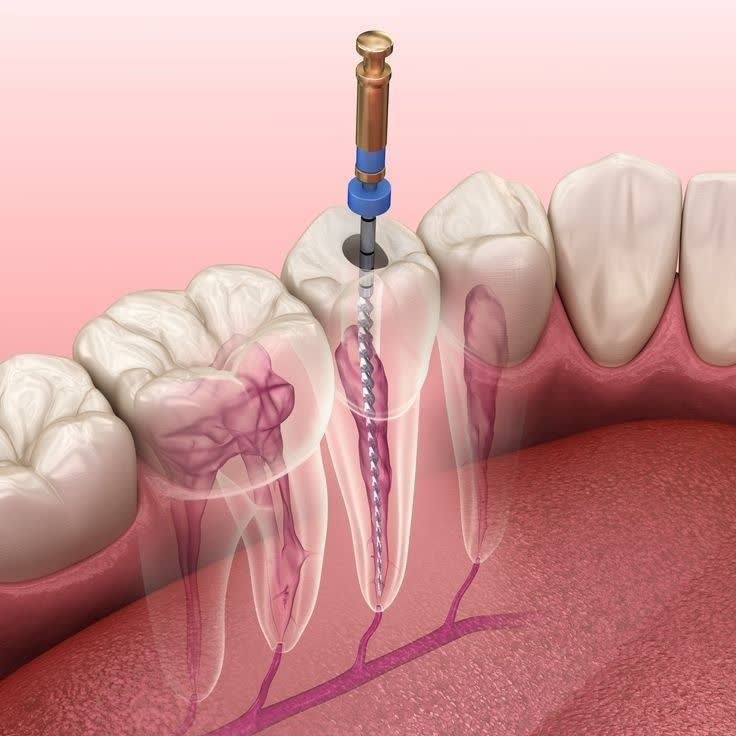

3- تهیه حفره برای دسترسی به پالپ (عصب دندان)

بعد از بی حس شدن کامل دندان، ابتدا پوسیدگی های تاج دندان حذف می شود و سپس راهی برای دسترسی به عصب دندان ایجاد می شود.

4- تمیز کردن کانال های ریشه

برای انجام عصب کشی دندان مورد نظر کانال های دندان تمیز می شوند و پس از آن فضای داخلی با مواد مخصوص پر می شود تا از نفوذ مجدد باکتری به داخل ریشه دندان جلوگیری شود.